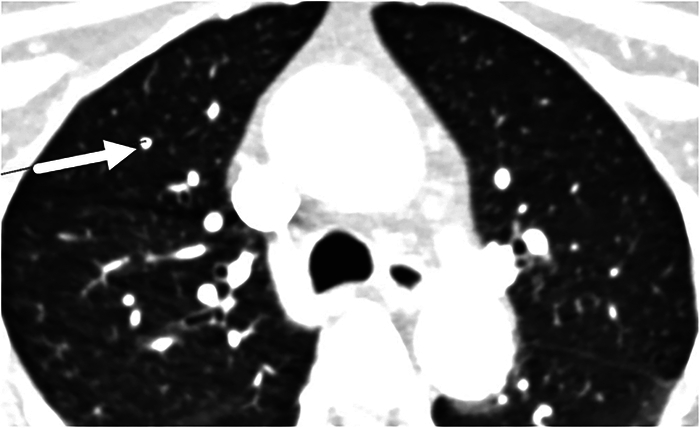

Purpose: Computed tomography angiography (CTA) of the head and neck includes the pulmonary apices, a common location for pulmonary nodules. Computer-aided detection (CAD) is an adjunctive tool for the detection of lung nodules and is widely used in standard chest CT scans. We evaluated whether the available software can be applied to CTA head and neck examinations, which include the lung apices, resulting in improved accuracy for lung nodule detection.

Materials and methods: In this retrospective single-center study, 191 previously reported head and neck CTA scans were re-evaluated for apical pulmonary nodules by 2 radiologists. Subsequently, CAD software ( Syngo .via, Siemens Healthiness AG) was applied to the lung apices and the results were compared between CAD and research radiologists (first reading) or clinical radiologist (null reading). In addition, the CAD performance in limited lung fields was compared with the accepted CAD assessment applied to whole lungs.

Results: Of the 191 patients, 110 (57.6%) were men, with a mean age of 68 years. In the 24 CT scans, the research radiologists detected 40 nodules. In the 180 scans evaluated by CAD, the software detected 39 nodules in 22 examinations, with a sensitivity of 60.8% and a PPV of 63.6%. In the remaining 158 examinations in which CAD did not detect nodules, the radiologists concurred in 149 scans, with a specificity of 94.9%, NPV of 94.3%, and accuracy of 90.6%.

Conclusion: The study results indicate that CAD is an unexpected quick supportive tool for nodule detection, particularly for excluding clinically significant nodules in lung apices on CTA head and neck, showing similar results for partial and full lung fields.